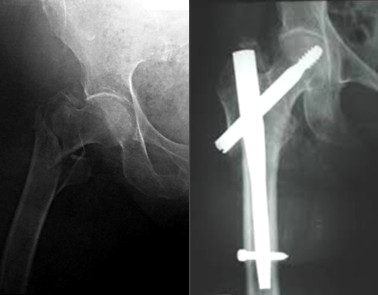

Остеосинтез бедренной кости штифтом типа гамма